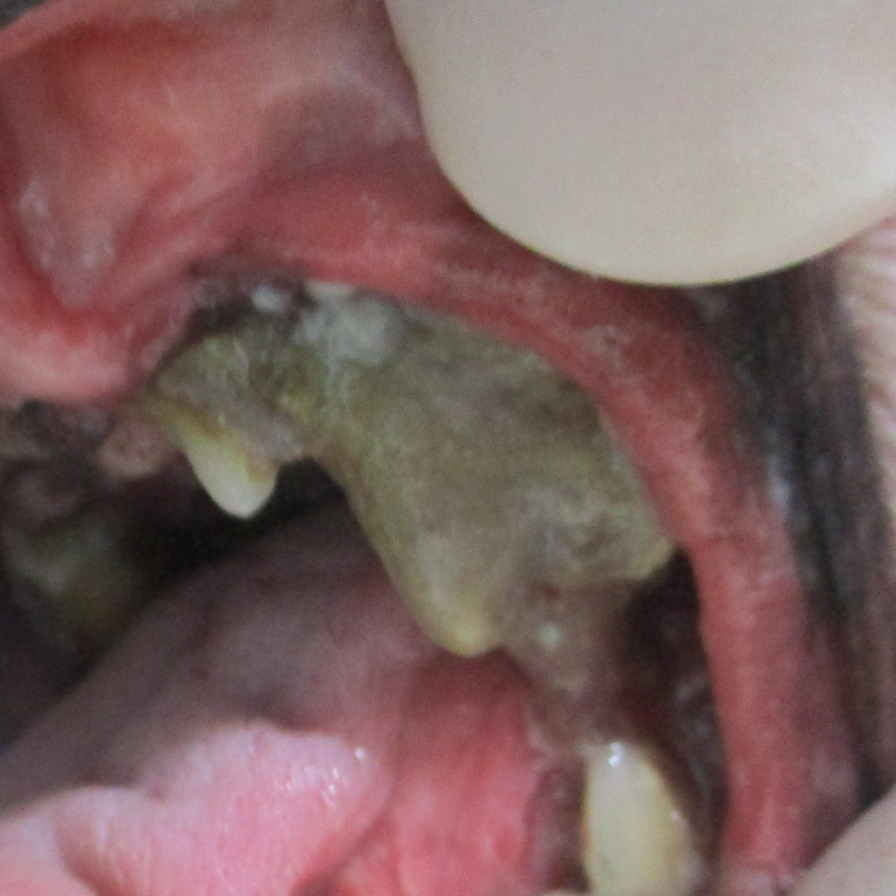

치석으로 잇몸, 치주 인대, 치조골이 다 녹아내린 모습. 치석 제거 전(왼쪽)과 후(오른쪽)의 모습

간혹 면역 반응이 심한 경우엔 치석과 닿는 볼 부위나 혀 부위에 궤양이 생기기도 해요. 이런 경우 약으로 조절이 되기는 하나 치석을 제거하지 않는 이상 약을 끊으면 다시 재발하게 돼요.

고양이의 경우 치석과 프라그가 쌓여서 그로 인해 구내염이 심하게 나타나는 경우가 있어요. 주로 면역 억제제를 이용하여 내과적으로 관리 하지만 스케일링도 함께 진행하면 더 좋은 효과를 볼 수 있어요.